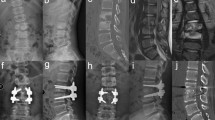

A monotubular caliper is presented, made out of a tube of drawn steel. It is lighter than a classical type of caliper, solid, safe, easy to put on and remove. Pressure points have been reduced to a minimum. Manufacturing is easy and delays shorter.